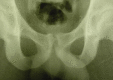

Conclusion: the surgical technique presented in this case series, with trapezoidal resection of the pubic symphysis in association with bilateral partial tenotomy of the long adductor, was a fast and effective procedure with a low rate of postoperative complications. It was shown to be an excellent treatment option for refractory cases, with a return to sports activity among professional soccer players.